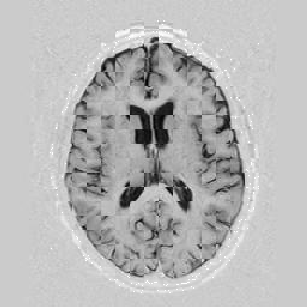

Another larger group of experiments enabled me to study the effects of multi-scale NRR. The results are shown in the form of chequerboard images in Figure [*]. In terms of resolution levels, higher numbers mean that the images are coarser.

Figure: Multi-scale NRR (increasing resolution). From left to right, top then bottom:before NRR; after 5 iterations of NRR at level 2 (higher is coarser); after another 5 iterations of NRR at level 1.